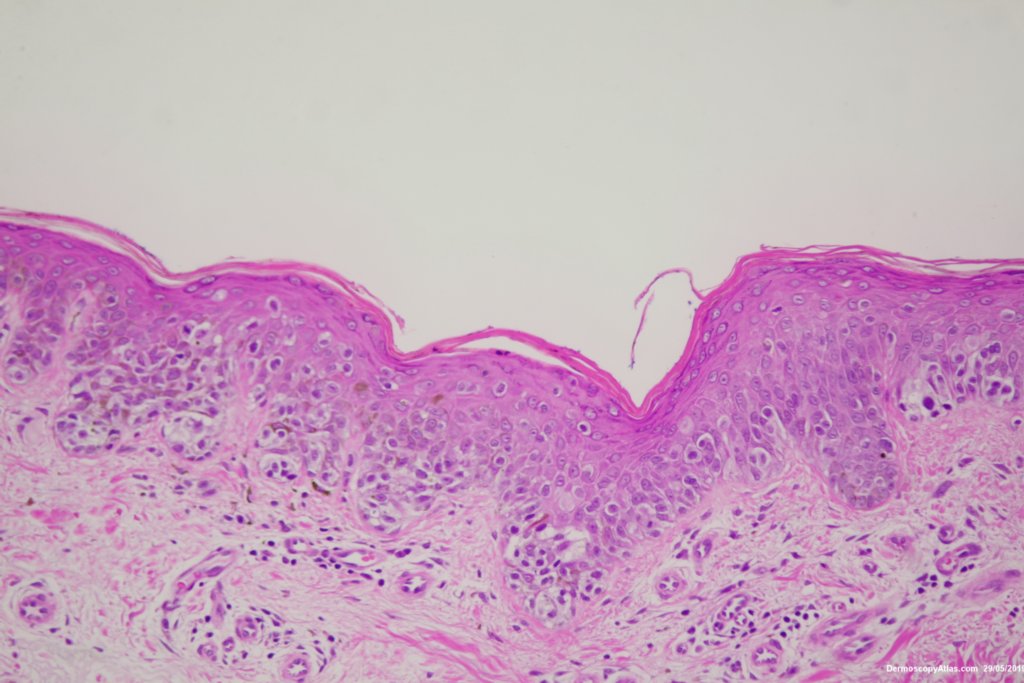

Image Number #3479 (Melanoma invasive)

Diagnosis: Melanoma invasive

Pigmented lesion on the lower leg noted at an annual skin check. The clinical is suggestive of a melanoma but the dermatoscopy was initially interpreted as coiled vessels with lines radial peripheral of an IEC. In IEC the lines radial are usually made up of dots but these are solid streaks. There is some vessel variability in the pink area.

This was an invasive melanoma 0.4 mm thick but the histology shown shows mainly in situ melanoma.Have a look at the second case in the video below for a more detailed overview of the histology.